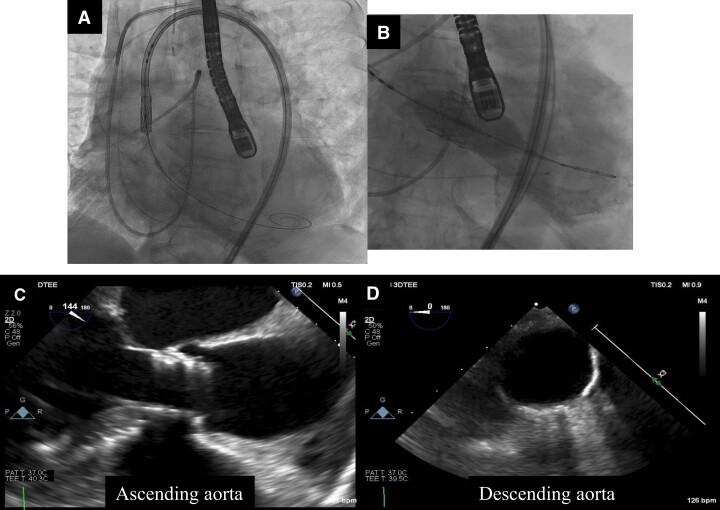

An 82-year-old woman presented with dyspnoea and general fatigue. Echocardiography revealed severe AS and she was diagnosed with heart failure associated with AS. She had difficulty controlling heart failure and required the intervention of the aortic valve. We evaluated the aortic valve and access routes with contrast-enhanced computed tomography (CT), which showed marked dilatation of the ascending aorta. Transcatheter aortic valve implantation was performed and the procedure was completed without major complications. Transoesophageal echocardiography during the procedure did not detect any obvious arterial injury. However, on the second postoperative day, the patient suddenly became unconscious and a CT indicated an ascending aortic dissection. Unfortunately, she passed away. An autopsy revealed the fragility of the ascending aorta.

一名82岁女性因呼吸困难和全身乏力就诊。超声心动图显示重度AS,她被诊断为与AS相关的心力衰竭。她在控制心力衰竭方面存在困难,需要进行主动脉瓣干预。我们通过增强计算机断层扫描(CT)评估了主动脉瓣和入路途径,结果显示升主动脉明显扩张。进行了经导管主动脉瓣植入术,手术过程顺利,未出现重大并发症。术中经食管超声心动图未发现任何明显的动脉损伤。然而,术后第二天,患者突然昏迷,CT显示升主动脉夹层。不幸的是,她去世了。尸检显示升主动脉脆弱。